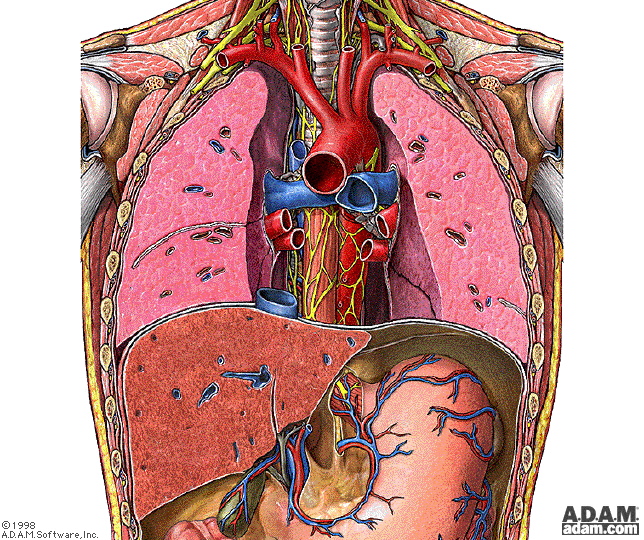

一、食管解剖

食管壁的组织结构:食管壁分4层:厚约3mm

外膜:缺乏浆膜,为疏松结缔组织,消化道中抗缝线拉力最弱的组织。